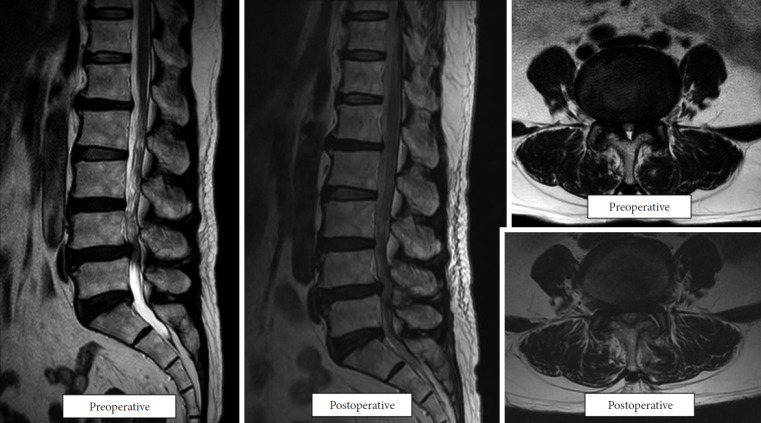

目的:本研究旨在评估采用双门静脉内镜脊柱手术(BESS)单侧椎板切开术进行双侧减压(ULBD)的临床和影像学结果,以治疗伴有或不伴有低级别退行性腰椎滑脱(DLS)的中央管狭窄患者。方法:对170例2015 - 2018年间行BESS-ULBD的患者进行回顾性观察研究,随访至少2年。将患者分为中枢性狭窄合并低度DLS的A组(68例)和单纯中枢性狭窄的B组(102例)。临床结果采用视觉模拟量表(VAS)评估背部和腿部疼痛、Oswestry残疾指数(ODI)和改良MacNab标准。放射学评估包括动态屈伸x线片矢状面平移测量。结果:两组在最终随访时均显著改善了临床结果(结论:BESS-ULBD是一种安全有效的微创治疗中央管狭窄的选择,无论有无低级别DLS。该技术可有效缓解症状,保持脊柱稳定性,并为精心挑选的患者提供了一种有希望的替代更具侵入性的融合手术。

Methods: A retrospective observational study was conducted on 170 patients who underwent BESS-ULBD between 2015 and 2018, with at least 2 years of follow-up. Patients were categorized into 2 groups: group A (68 patients) with central stenosis and low-grade DLS and group B (102 patients) with central stenosis alone. Clinical outcomes were assessed using the visual analogue scale (VAS) for back and leg pain, Oswestry Disability Index (ODI), and Modified MacNab criteria. Radiological assessments included sagittal translation measurements on dynamic flexion-extension radiographs.

Results: Both groups significantly improved clinical outcomes at the final follow-up (p<0.05). Group A's mean VAS scores improved from 3.8±2.4 to 1.9±2.0 for back pain and from 6.4±1.8 to 2.3±2.0 for leg pain. In group B, back pain improved from 3.9±2.5 to 1.7±1.9, and leg pain from 6.6±2.0 to 2.2±2.2. ODI scores also improved significantly in both groups. Radiological evaluation showed no significant changes in sagittal translation postoperatively, indicating preserved spinal stability. Both groups had comparable clinical outcomes, with no major complications reported.

Conclusion: BESS-ULBD is a safe and effective minimally invasive option for managing central canal stenosis, with or without low-grade DLS. This technique provides substantial symptom relief, preserves spinal stability, and presents a promising alternative to more invasive fusion procedures in carefully selected patients.